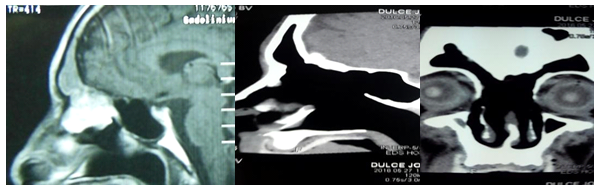

In some patients, for the lateral technique, the anterior third of the middle turbinate was then resected bilaterally. The antero-superior sector of the nasal septum, between both ostiums, was removed creating a common cavity for drainage of the frontal sinus. The obtained limits were, laterally both lamina papyracea of the ethmoid bone, anteriorly the nasal bones and posteriorly the cribiform plate and posterior wall of the frontal sinus. Fig.1 In other patients, the medial technique (outside-in) was performed: a mucosal flap was dissected anterior to the medial turbinate, on the frontal processes of the maxilla to identify the first olfactory nerve fiber. An anterior and superior septectomy, of approximately 1 centimeter, was made, and the frontal sinus was then approached in the most anterior part, by drilling the nasal bones. The drainage was extended to the posterior part of the sinus and laterally to both lamina papyracea. Medtronic Integrated Power Console lathe was used with diamond and cutting burrs of different diameters, curettes and a Kerrison-type rongeur. The mucosa of the lateral wall of the frontal sinus (lamina papyracea), responsible of the mucociliary transport, was preserved. A septal mucosal-free graft was used in some patients to cover the exposed bone anterior part of the sinus. The optical neuronavigation system was used in most of the patients ((Figure 1, Figure 2).

Figure 1 Modified Lothrop technique.

Figure 2 Optical neuronavigation systems.